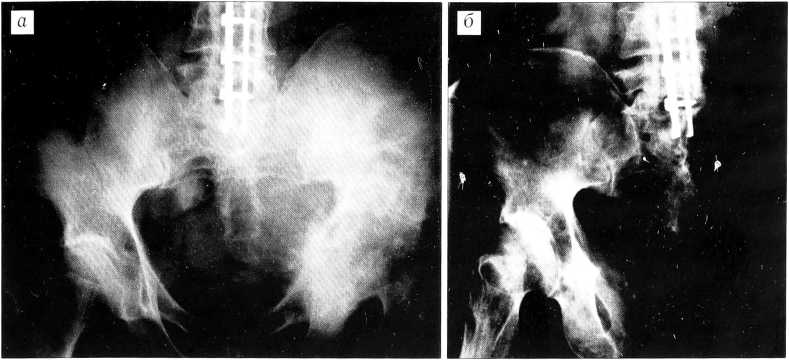

Больной П., 37 лет. За 1 год 2 мес до поступления появились боли в правой ягодичной области, которые связывал с незначительной травмой. Лечился у невропатологов физиотерапевтическими методами. Боли нарастали, и после дополнительного обследования диагностирована хондросаркома костей таза. Больной признан неоперабельным из-за распространения опухоли в область ягодицы и на крестец.

При обследовании в нашей клинике определяется больших размеров плотная опухоль, занимающая область крестцово-подвздошного сочленения и большую часть ягодицы. Размер пальпируемой части опухоли 20x20 см. Рентгенография, компьютерная томография и ангиография: в крыле правой подвздошной кости и правой боковой массе крестца очаг деструкции преимущественно остеолитического характера, неоднородной структуры за счет наличия более плотных участков, с мягкотканным компонентом в ягодичной области. Контуры очага и замыкательных пластинок крестцово-подвздошного сочленения нечеткие. Отмечаются мелкоочаговые разрежения структуры в видимых отделах правой бедренной кости, лонной и седалищной костях (рис. 4). В легких патологических изменений не выявлено.

Рис. 4. Рентгенограмма (а), компьютерная томограмма (б) и ангиограмма (в) больного П. Хондросаркома таза.

Несмотря на широкое распространение опухоли на область ягодицы и характер процесса, учитывая отсутствие альтернативных методов лечения, решено предпринять попытку межподвздошно-брюшной экзартикуляции с резекцией крестца.

11.01.00 больному произведена операция. Из разреза, начатого от уровня остистого отростка L2 позвонка, идущего вдоль всего гребня левой подвздошной кости до передней верхней ости и вдоль паховой связки, а затем продолженного на передневнутреннюю поверхность бедра до его средней трети, осуществлен широкий внутритазовый доступ. Выделены сосуды от общей подвздошной артерии до средней трети бедра. Внутренняя подвздошная артерия перевязана и пересечена. Пересечены и отделены поясничные мышцы, прикрепляющиеся к крестцу и гребню подвздошной кости, а внутритазово — пояснично-подвздошная мышца на уровне крестцово-подвздошного сочленения. Пересечены нервные корешки, формирующие левый седалищный нерв, а также бедренный нерв. Кожный разрез проведен по паховой складке до соединения с разрезом на бедре. Пилой Джильи, проведенной вокруг боковой массы крестца, пересечен крестец на границе его боковой массы и тела. В разрезе была видна твердая мозговая оболочка, которая оставалась неповрежденной. В зоне пересечения крестца опухоль не была вскрыта. Для закрытия раны, занимавшей всю тазовую и ягодичную область и левую половину брюшной полости, сформирован кожно-фасциально-мышечный лоскут с включением в него четырехглавой и части приводящих мышц бедра, васкуляризация которых осуществлялась наружными бедренными сосудами, пересеченными в средней трети бедра. Сформированный лоскут был подшит к крестцу и закрыл рану целиком. Гистологическое исследование опухоли: миксоидная хондросаркома с разрушением подвздошной кости и распространением на большую часть ягодичных мышц. В зоне пересечения препарата опухолевых клеток не обнаружено.